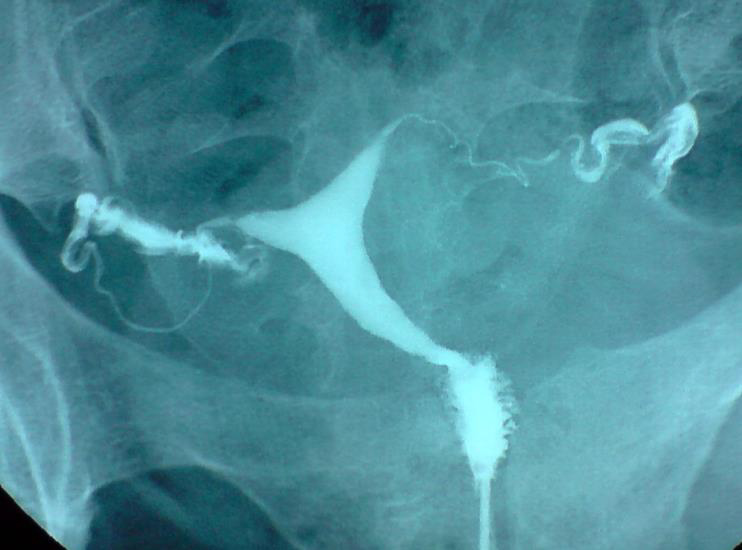

Le test de perméabilité des trompes

Soit l’hystérosalpingographie réalisée en cabinet de radiologie, soit l’HYFOSY réalisée par votre gynécologue ou un par un échographiste spécialisé. Dans les deux cas, un produit de contraste est instillé dans la cavité utérine, et la perméabilité tubaire est évaluée.